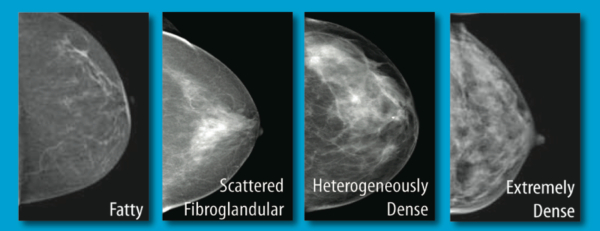

Early research has shown that 3D mammography can improve breast cancer detection rates and reduce false-positive rates. In women with dense breast tissue, which can mask cancers on conventional mammography, 3D mammography is emerging as a valuable supplemental screening tool.

3D Mammography and Breast Density

Women with dense breast tissue should seek clarity from their doctors on what might be the most appropriate supplemental screening exam. Although advice for a woman must be individualized, formal screening recommendations may one day include 3D mammography.